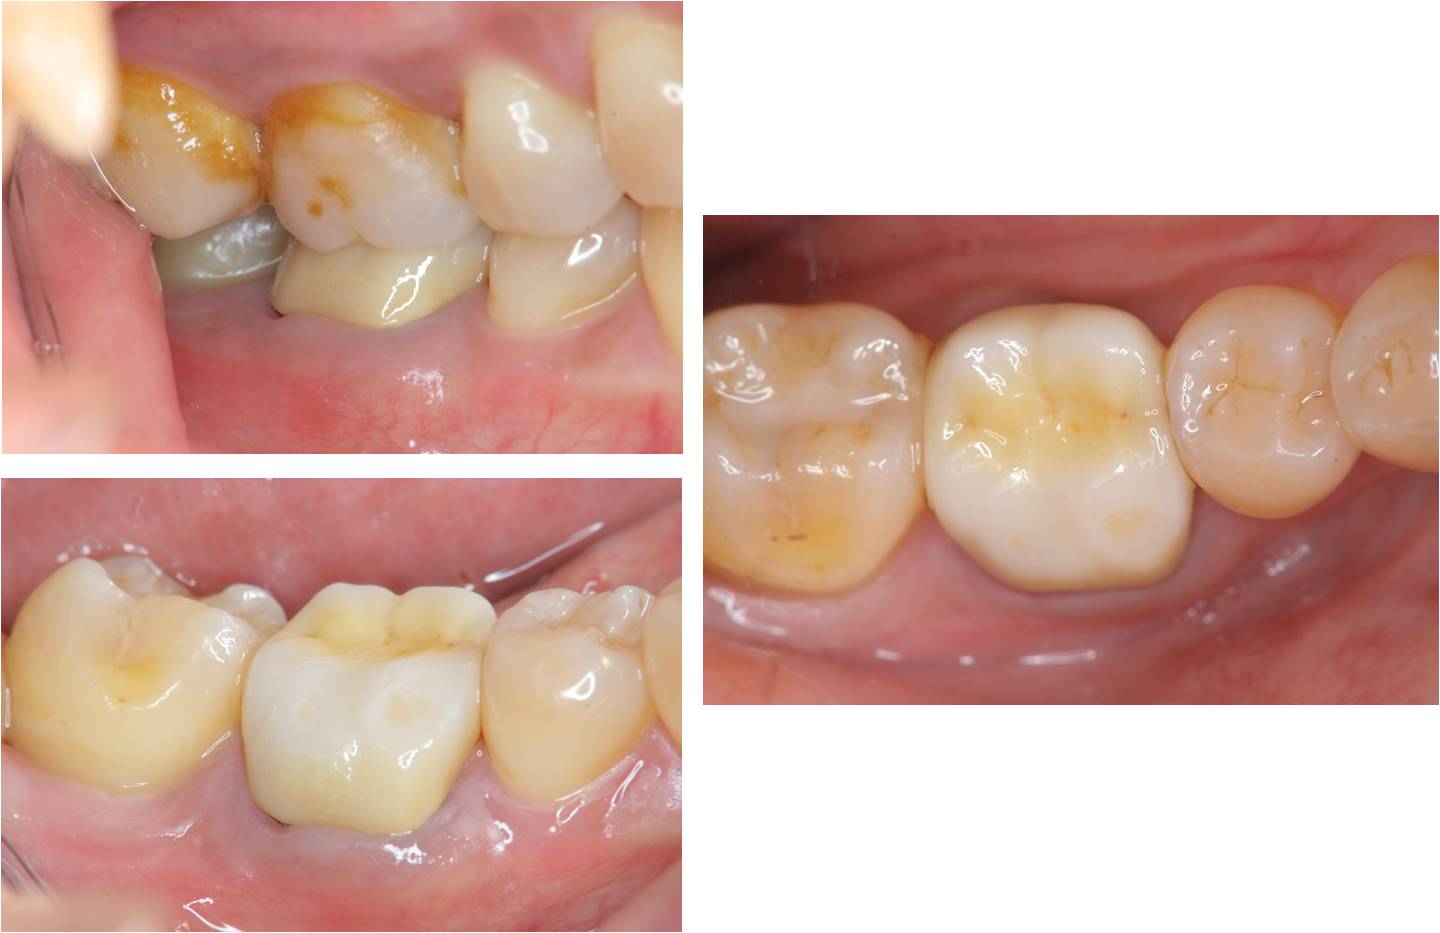

治療前,假牙崩壞

全瓷冠牙齒製備

臨床照相比色

治療後,口內適應良好

牙齒邊緣密合度良好

術前、術後比較